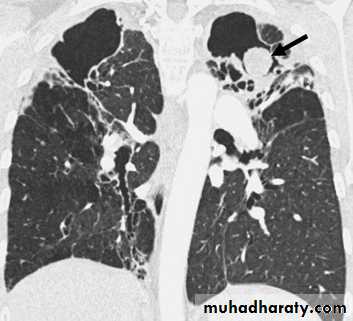

Nodular (coin) lesion in the left upper lung with irregular edge (most probably cancinoma